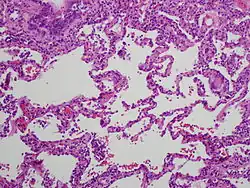

| High magnification photomicrograph of a lung biopsy taken showing chronic hypersensitivity pneumonitis (H&E), showing mild thickening of the walls of the small air sacs by invasion of white blood cells. A multinucleated giant cell, seen within the walls of the air sacs to the right of the picture halfway down, is an important clue to the correct diagnosis. | |

Lung biopsy

Lung biopsies can be diagnostic in cases of chronic hypersensitivity pneumonitis, or may help to suggest the diagnosis and trigger or intensify the search for an allergen. The main feature of chronic hypersensitivity pneumonitis on lung biopsies is expansion of the interstitium by lymphocytes accompanied by an occasional multinucleated giant cell or loose granuloma.[7][22]

When fibrosis develops in chronic hypersensitivity pneumonitis, the differential diagnosis in lung biopsies includes the idiopathic interstitial pneumonias.[23] This group of diseases includes usual interstitial pneumonia, non-specific interstitial pneumonia and cryptogenic organizing pneumonia, among others.[7][22]

The prognosis of some idiopathic interstitial pneumonias, e.g. idiopathic usual interstitial pneumonia (i.e. idiopathic pulmonary fibrosis), are very poor and the treatments of little help. This contrasts the prognosis (and treatment) for hypersensitivity pneumonitis, which is generally fairly good if the allergen is identified and exposures to it significantly reduced or eliminated. Thus, a lung biopsy, in some cases, may make a decisive difference.